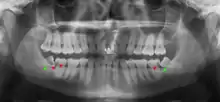

Panoramic radiograph of impacted lower wisdom teeth (green arrows) in a 26-year-old with dental caries (red arrows) on the adjacent teeth

Impacted 2nd molar (red arrow) with developing wisdom tooth (green arrow)

There is no standard to screen for wisdom teeth. It has been suggested, absent evidence to support routinely retaining or removing wisdom teeth, that evaluation with panoramic radiograph, starting between the ages of 16 and 25 be completed every 3 years. Once there is the possibility of the teeth developing disease, then a discussion about the operative risks versus long-term risk of retention with an oral and maxillofacial surgeon or other clinician trained to evaluate wisdom teeth is recommended. These recommendations are based on expert opinion level evidence.[19] Screening at a younger age may be required if the second molars (the "12-year molars") fail to erupt as ectopic positioning of the wisdom teeth can prevent their eruption. Radiographs can be avoided if the majority of the tooth is visible in the mouth.